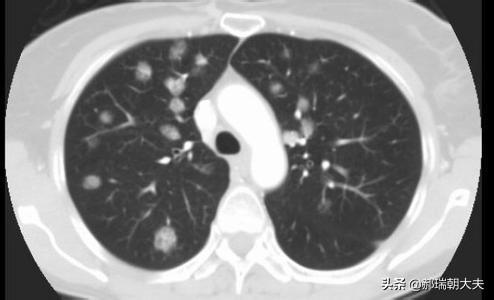

多発性肺結節と孤立性肺結節があり、多発性肺結節は結核やじん肺に続発することが多く、いずれも典型的な病歴や左葉の病歴で診断しやすい。我々が一般的に論じる結節は孤立性肺結節を指す。

現在受け入れられている肺結節の定義は、直径3cm以下の限局性、円形、高密度、固形または亜固形の肺影である。 近年、低線量CTによるスクリーニングを受ける人口が増加するにつれて、孤立性肺結節に加えて多発性肺結節が検出される割合がかなり増加している。多発性肺結節は多くの場合、1個の肺結節と1個以上の小結節として現れる。多発性肺結節は2個以上の病変として定義される。多発性肺結節を有する患者は、外科的に確認され、臨床的に重大な注意を要する早期肺癌または前癌病変の複数の発生源を有する可能性がある。

肺結節:肺の組織に現れる病変である。直径30mm以下の円形または不規則な病変で、正常な肺組織に囲まれていることが多い。医用画像では「肺の高密度陰影」と表現される。肺小結節は単結節または多結節で、境界が明瞭なものと不明瞭なものがある。

病変の数によって、肺結節は孤立性肺結節、多発性肺結節、びまん性肺結節に分類される。

結節密度の均一性によって、実質的な結節、純粋な挽きガラス結節、混合挽きガラス結節に分類される。